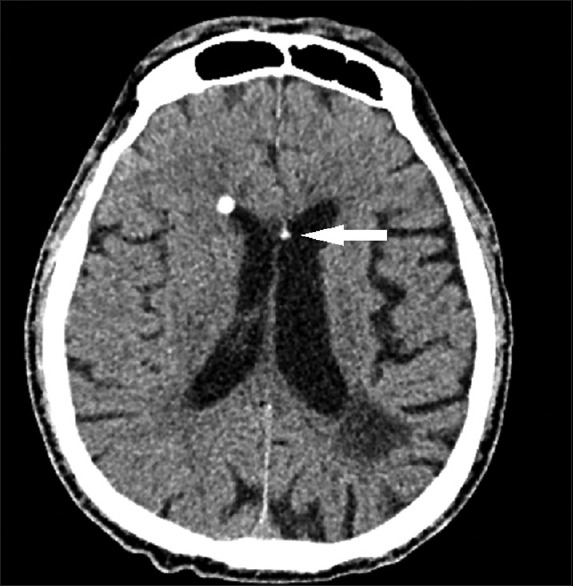

Intraventricular and subarachnoid migration of silicone oil from previous intraocular injection mimicking intracranial haemorrhage: a case report.